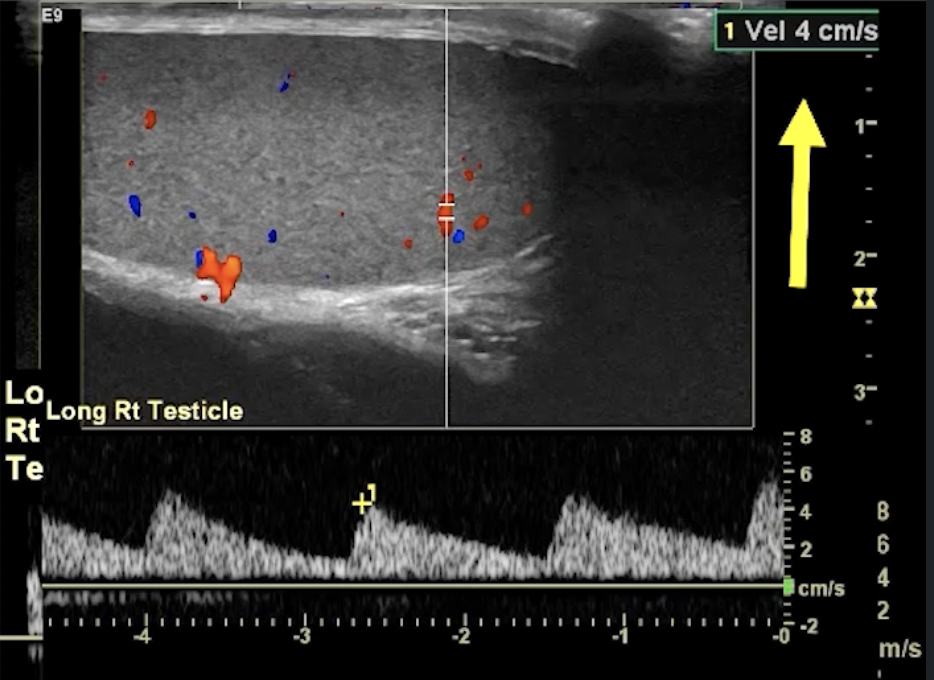

• Partial Torsion

• May have some blood flow

• Decreased or reversal of flow in diastole (no line in between peaks) - indicates high resistance state (top images)

• Blunted arterial peak (not as sharp as a point in systole) ( bottom images)